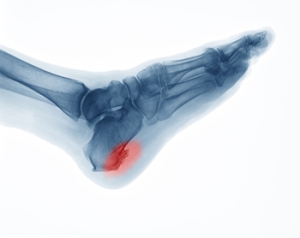

What Are Heel Spurs?

There are many conditions that can cause discomfort in the heel, but one of the most common is heel spurs. A small calcium deposit forms and can eventually extend from your heel bone to your arch. Symptoms associated with heel spurs are pain, inflammation, and swelling at the front of your heel. The heel might also feel warm, and over time, a small protrusion could be visible. Some heel spurs can go unnoticed and only become apparent on an X-ray. Heel spurs develop over time, so they will not suddenly appear. Distinguishing heel spurs from other conditions that cause heel pain can be hard to do on your own, so if you are experiencing heel pain then it is suggested that you speak with a podiatrist who can properly diagnosis you.

Heels Spurs

Heel spurs are formed by calcium deposits on the back of the foot where the heel is. This can also be caused by small fragments of bone breaking off one section of the foot, attaching onto the back of the foot. Heel spurs can also be bone growth on the back of the foot and may grow in the direction of the arch of the foot.

Older individuals usually suffer from heel spurs and pain sometimes intensifies with age. One of the main condition's spurs are related to is plantar fasciitis.

Heel Spurs

Heel spurs are the result of calcium deposits that cause bony protrusions on the underside of the heel. Heel spurs are usually painless, but they have the potential to cause heel pain. Heel spurs tend to be associated with plantar fasciitis, which is a condition that causes inflammation of the band of connective tissue that runs along the bottom of the foot. They most often occur to athletes whose sports involve a lot of running and jumping.

It is possible to have a heel spur without showing signs of any symptoms. However, if inflammation develops at the point of the spur’s formation, you may have pain while walking or running. In terms of diagnosis, sometimes all a doctor needs to know is that the patient is experiencing a sharp pain localized to the heel to diagnose a heel spur. Other times, an x-ray may be needed to confirm the presence of a heel spur.